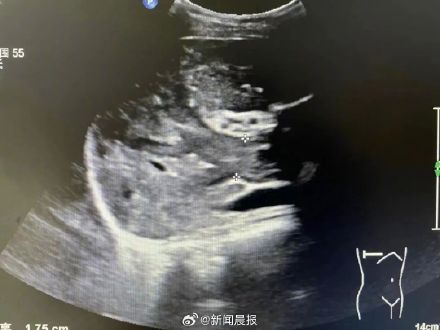

前段时间,小丽感到肚子不舒服,自己吃了些胃药,但腹部的不适一点都没有改善。她前往丽水市中心医院就诊,超声提示肝内肿瘤伴门静脉广泛癌栓。最终确诊为“肝癌晚期” “我孩子才3岁,我才24岁,怎么就一下子成肝癌晚期了呢,平时也没有什么不舒服。”小丽确诊肝癌晚期后,一下子嚎啕大哭了起来。

市中心医院超声医学科陈志辉介绍,肝脏是沉默的器官,它的代谢功能很强,正常人只需要1/3的肝脏,就能维持日常生理功能需要。因此肝脏恶性肿瘤,早期往往没有任何症状。当肿块增大到一定大小,影响到肝脏功能时,会出现乏力、食欲下降、厌油,上腹部饱胀不适等症状,而这些症状不具有特异性,往往被认为是工作太辛苦、压力大,甚至被当成肠胃病等。当出现肝区疼痛,这时可能已到了肝癌中晚期。陈志辉说,从检查看,小丽是典型的从乙肝发展为肝癌的患者。

“如果早点发现乙肝,做好随访,及时治疗干预,她就不会在这么年轻的时候确诊肝癌晚期。”陈志辉介绍,前段时间,有个26岁单身女青年来医院进行单位组织的体检,验血结果显示AFP超过2000ng/ml,超声提示肝内肿瘤。后来经过住院检查确诊为早期肝癌。经过肝癌根治手术,目前已经康复出院。 当前,肝癌患者越来越年轻化,而且绝大多数是像小丽这样,对自己的健康状态“太过自信”,发现时已是晚期。